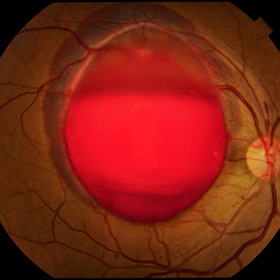

dislocated crystalline lens

Male patient 54-years-old. In the preoperative follow-up of cataract surgery, he suffered blunt trauma to the right eye, with a total dislocation of the lens.

Photographer: JEFFERSON R SOUSA - Study Center and Ophthalmological Research Dr. Andre M V Gomes, Institute Dr. Suel Abujamra São Paulo-Brazil

Imaging device: Topcon TRC-50 DX, Imaginet 5.0, angle de 50 graus. Flash 18W-S

Condition/keywords: dislocated crystalline lens

Dislocated Intraocular Lens (IOL)

A 53-year-old male patient suffered blunt trauma 15 days after cataract surgery. Note total dislocation of the intraocular lens. No glass reaction.

Imaging device: Topcon TRC-50 DX, Imaginet 4.0, angle de 50 graus. Flash 18w-s

Condition/keywords: dislocated intraocular lens (IOL)